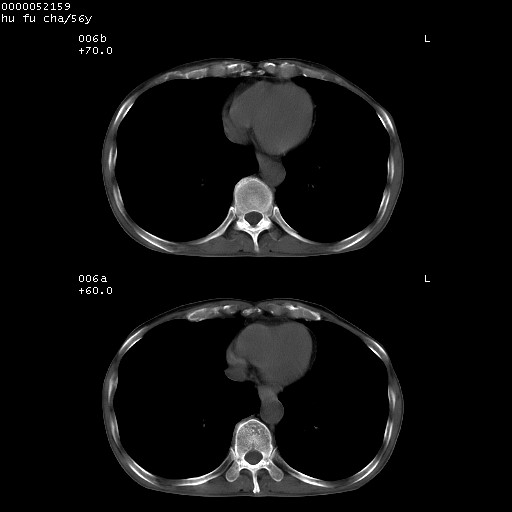

以下是引用zsl6918在2008-8-25 22:47:00的发言:[br]胸骨,胸椎及肋骨均可见多发转移表现,肝内低密度结节不除外转移。原发灶可能在右肺。双侧可见支扩表现。

以下是引用宇宙ct在2008-8-25 23:26:00的发言:[br][br] 胸骨,胸椎及肋骨均可见多发转移表现,肝内低密度结节不除外转移。原发灶可能在右肺。双侧可见支扩表现。 [br] [br]

以下是引用卜一在2008-8-26 8:02:00的发言:[br][br] 支持:肺癌并肺内,胸骨,胁骨,胸椎及肝内转移!另:左肺支气管扩张征伴感染! [br]

以下是引用zjzjr在2008-8-26 11:03:00的发言:[br]支持:肺癌并肺内,胸骨,胁骨,胸椎及肝内转移!另:左肺支气管扩张征伴感染!